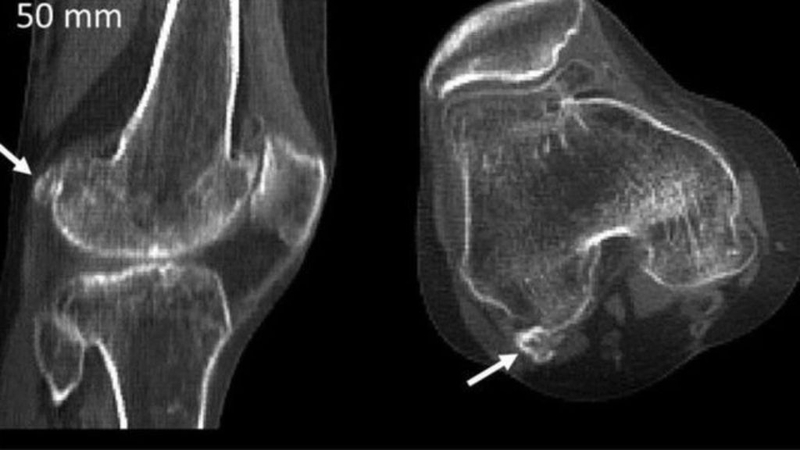

Sự xuất hiện của xương vừng Fabella trong cơ thể gây ra nhiều tranh cãi về sự hình thành của chúng. Có giả thuyết cho rằng xương Fabella được hình thành từ trong thời kỳ bào thai tuy nhiên sau đó xảy ra canxi hoá. Một số nghiên cứu đã chỉ ra rằng xương Fabella có 3 hình thái cấu trúc khác nhau, đó là cấu trúc xương, cấu trúc sợi và cấu trúc sụn sợi. Sự hình thành của xương vừng Fabella đôi khi dễ gây ra nhầm lẫn là tổn thương trong bệnh lý u sụn màng hoạt dịch hay các bệnh lý thoái hóa khớp.